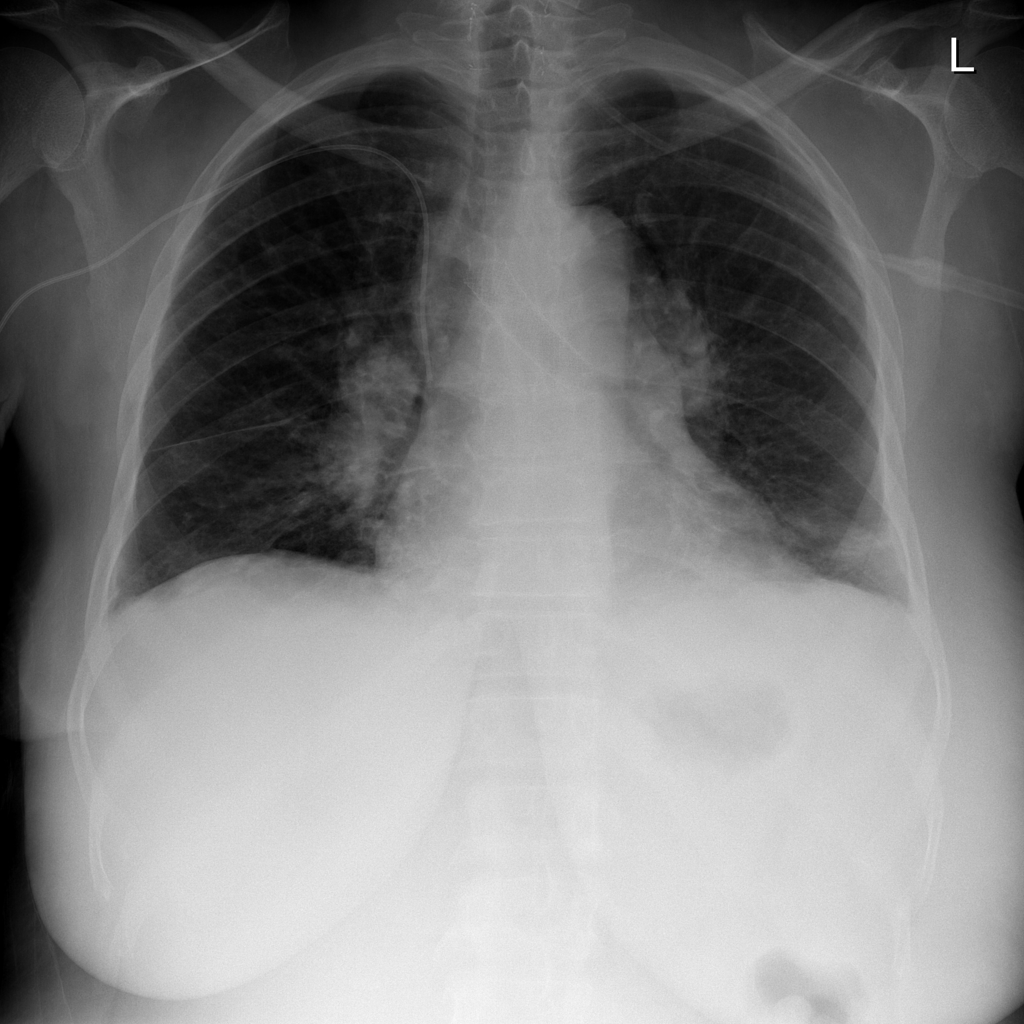

Mass representative X-ray

Reference image: PAT-4F3F · IMG-024 · Bounding-box highlight from source annotation where available.

• On chest X-ray, a mass often appears as a relatively well-defined focal opacity larger than a nodule

• Shape, border, density, and location all affect interpretation